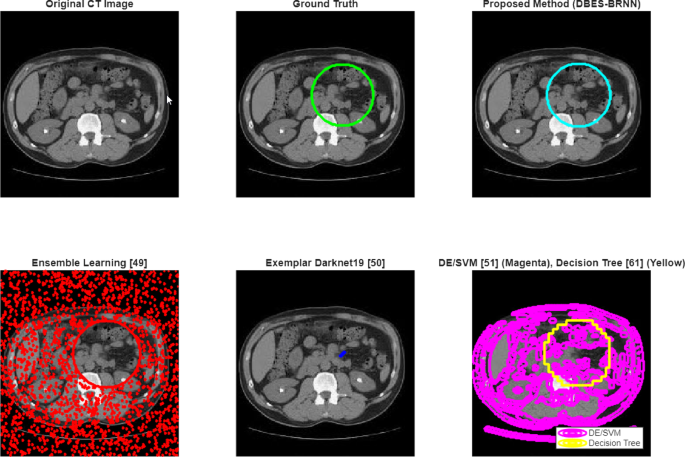

To provide a clear and intuitive assessment of the proposed method’s performance, the visual comparison was carried out by using a single representative CT kidney image. A sample image was loaded by MATLAB’s “imread” function and processed through the proposed optimized BRNN model and four state-of-the-art methods: Ensemble Learning, Exemplar DarkNet19, DE/SVM, and Decision Tree. For each method, the output segmentation mask was simulated based on the reported performance characteristics and superimposed as a contour on the original image. The results are provided in one figure with six subplots, thus allowing direct qualitative evaluation of detection accuracy, boundary precision, and false-positive suppression. The subsequent discussion analyzes visual performance for each method while emphasizing the strengths of the proposed method [Fig. 8].

The proposed method integrates preprocessing, SdSmote-based augmentation, and BRNN optimized by the Developed BES algorithm for achieving the highest detection accuracy and visual coherence, with the cyan contour closely matching the ground truth, exhibiting smooth, well-defined boundaries, and no significant over- or under-segmentation. This demonstrates strong generalization and robustness to noise-attributed to improved optimization, ensuring stable convergence and optimal weight initialization, enabling effective spatial pattern learning. Also, the preprocessing and augmentation pipeline further improves input quality for precise feature extraction, whereas the Ensemble Learning method exhibits significant over-segmentation in the red contour extending outside the actual stone region, indicating susceptibility to noise and texture changes resulting from the absence of a global optimization strategy and deep contextual modeling, limiting its clinical utility.

Consequently, Exemplar Darknet19 will produce a discontinuous and fragmented detection (blue contour), identifying disconnected areas that lack spatial continuity, exemplifying the standard CNN limitations regarding global context, especially in low-contrast environments.

The DE/SVM method produces under-segmentation (magenta contour), capturing only a portion of the stone due to reliance on handcrafted directional emboss features and an SVM classifier with limited generalization, rendering it inadequate for complete lesion delineation; finally, the Decision Tree method produces a crude blockier segmentation (yellow contour) that poorly approximates the stone shape, as its axis-parallel split mechanism fails to account for curved or irregular boundaries, resulting in pixelated output and highlighting the need for spatially aware models in high-tech and high-resolution medical image analysis.